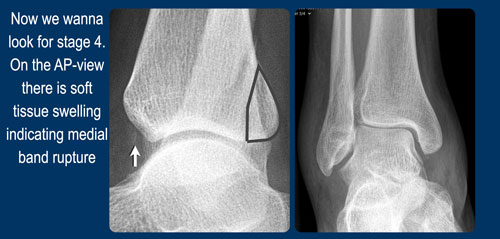

- Gãy bong điểm bám mắt cá trong hoặc đứt các bó dây chằng bên trong (medial collateral bands)

Khi phát hiện gãy xương Weber B — vốn luôn hiện rõ trên tư thế chụp thẳng (AP) hoặc tư thế chụp nghiêng — điều duy nhất cần kiểm tra là liệu có tổn thương giai đoạn 3 không ổn định với tổn thương phía sau, hay thậm chí giai đoạn 4 với tổn thương phía trong hay không.

Khi xương sên đẩy mảnh xương mác về phía sau, lực căng tại khớp chày mác sau (syndesmosis sau) sẽ gây đứt dây chằng hoặc bong mắt cá thứ ba (malleolus tertius). - Phía trong

Khi xương sên tiếp tục di chuyển ra sau ngoài, lực căng rất lớn tác động lên dây chằng bên trong (dây chằng delta) sẽ gây đứt dây chằng hoặc bong mắt cá trong.